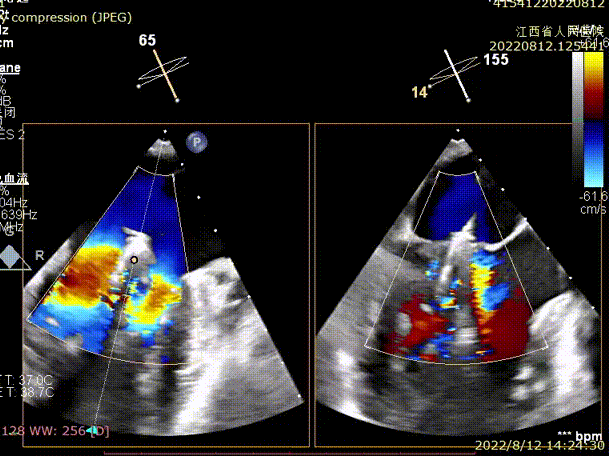

手术于全麻下进行,采用经典股静脉房间隔途径,房间隔穿刺后置入24F导引导管及二尖瓣夹输送系统,在TEE引导下准确植入一枚二尖瓣夹至A2/P2区,瓣膜夹位置稳定,植入后反流下降至1+,二尖瓣跨瓣平均压力阶差1mmHg,双孔化形成,遂移除器械输送系统。超声心动图评估瓣膜夹位置和功能良好,瓣膜夹活动度低,手术顺利完成。

术后TEE显示,二尖瓣夹植入后反流减少